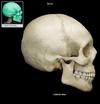

Temporals Flashcards

(12 cards)

1

Temporal Squama

2

External auditory meatus

Zygomatic process of the temporal

Supramastoid crest

Mastoid process